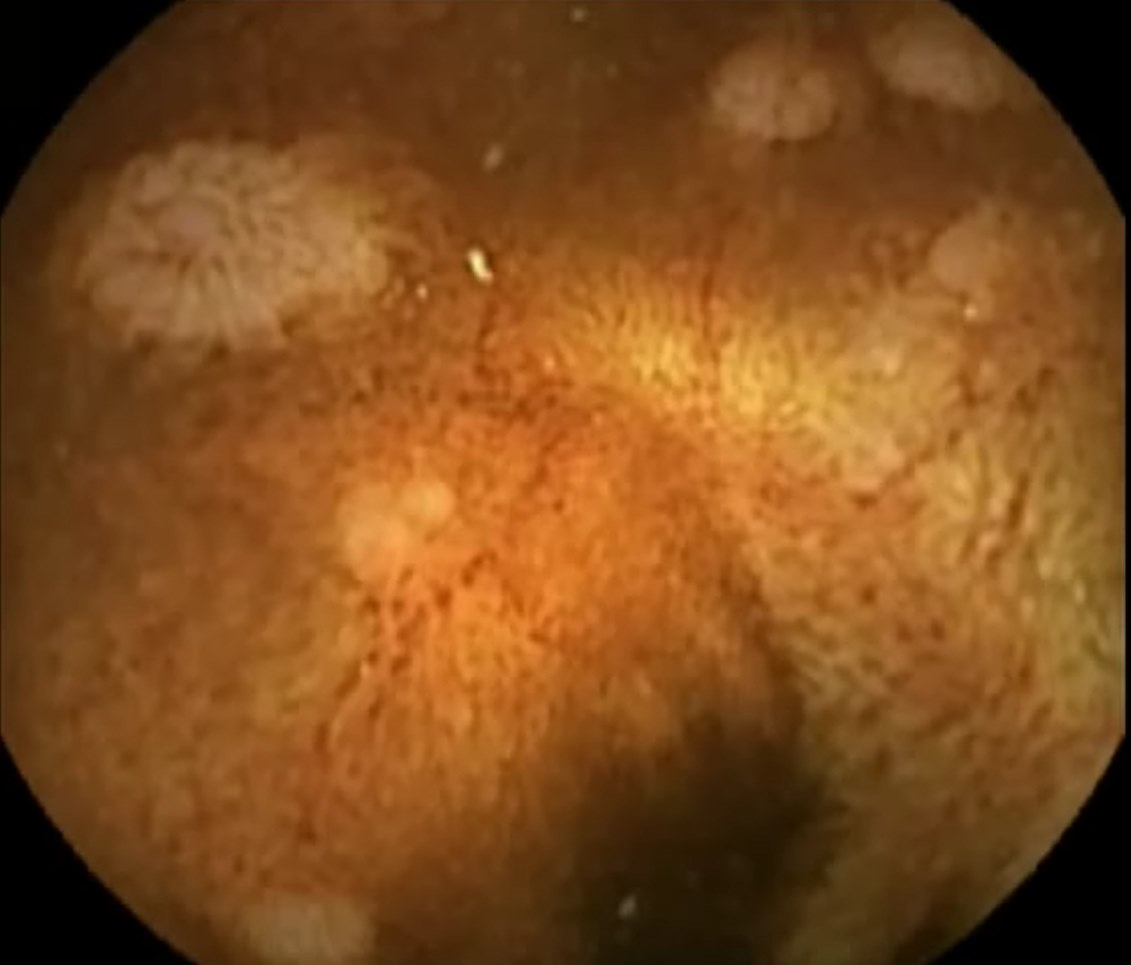

Capsule Endoscopy: Ileum Terminale, Lymphoid Hyperplasia

Capsule Endoscopy: Ileum Terminale, Lymphoid Hyperplasia. Just click on a picture!